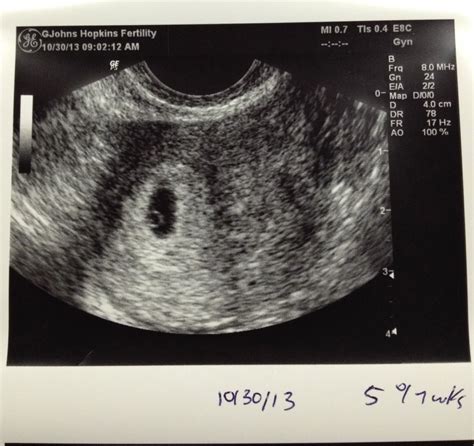

A 5 weeks pregnant sonogram is typically performed transvaginally due to the early stage of pregnancy. This method provides a clearer image of the uterus and the developing embryo. At this stage, the embryo is still very small, measuring about 2 millimeters in length, which is roughly the size of a sesame seed. The sonogram can detect the gestational sac, which is a fluid-filled structure that will eventually house the embryo.

• Results: The technician will capture images of the gestational sac and may be able to see the yolk sac, which provides early nourishment to the embryo.

It's important to note that at 5 weeks, the embryo itself may not be visible on the ultrasound. The primary focus is on confirming the presence of the gestational sac and ensuring that the pregnancy is progressing normally.

• Gestational Sac: A fluid-filled structure that houses the developing embryo.

• Yolk Sac: A small, round structure that provides early nourishment to the embryo.

• Embryo: At 5 weeks, the embryo itself may not be visible, but the gestational sac and yolk sac are important indicators of a healthy pregnancy.